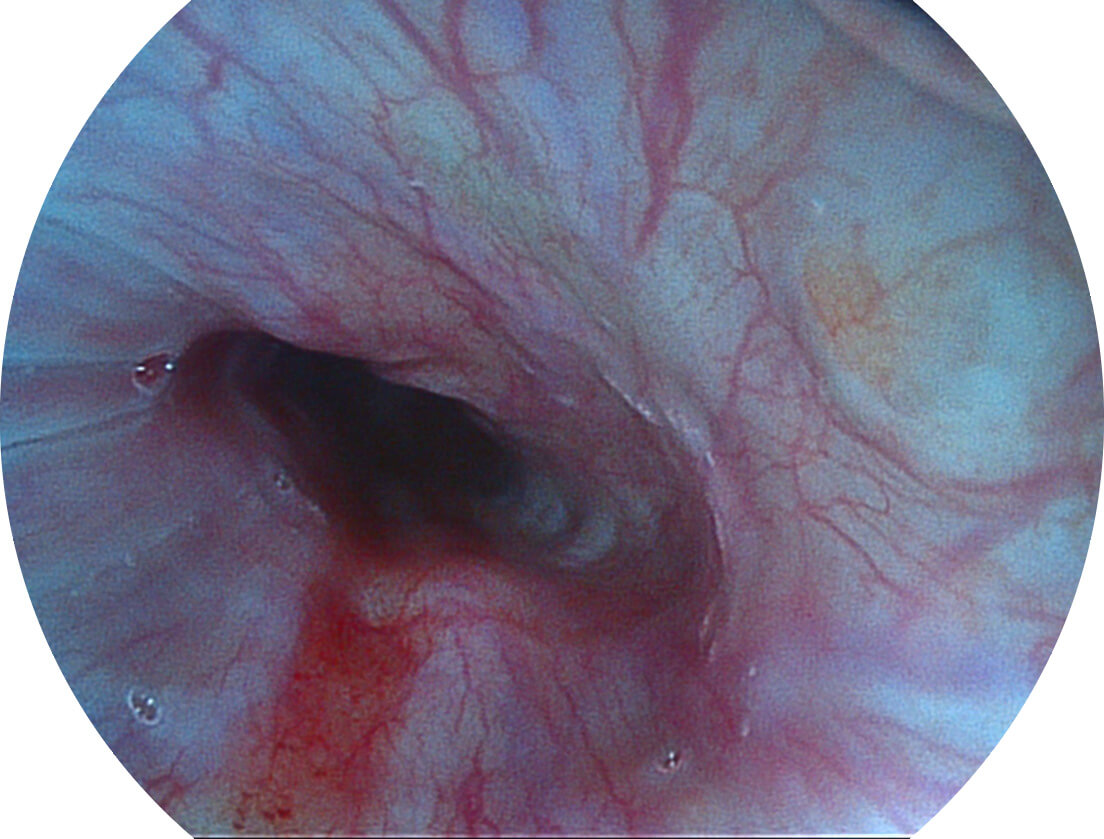

Versatile Intelligent Staining Technology, VIST

强调浅层黏膜结构的同时,保证照明亮度和提升浅层微血管与中层血管颜色对比度,病变边界更清晰。

采用光路合束技术,光谱自由度高,实现了更丰富的照明模式,染色模式SFI及VIST,从远景到近景,助力消化道早期疾病诊断。